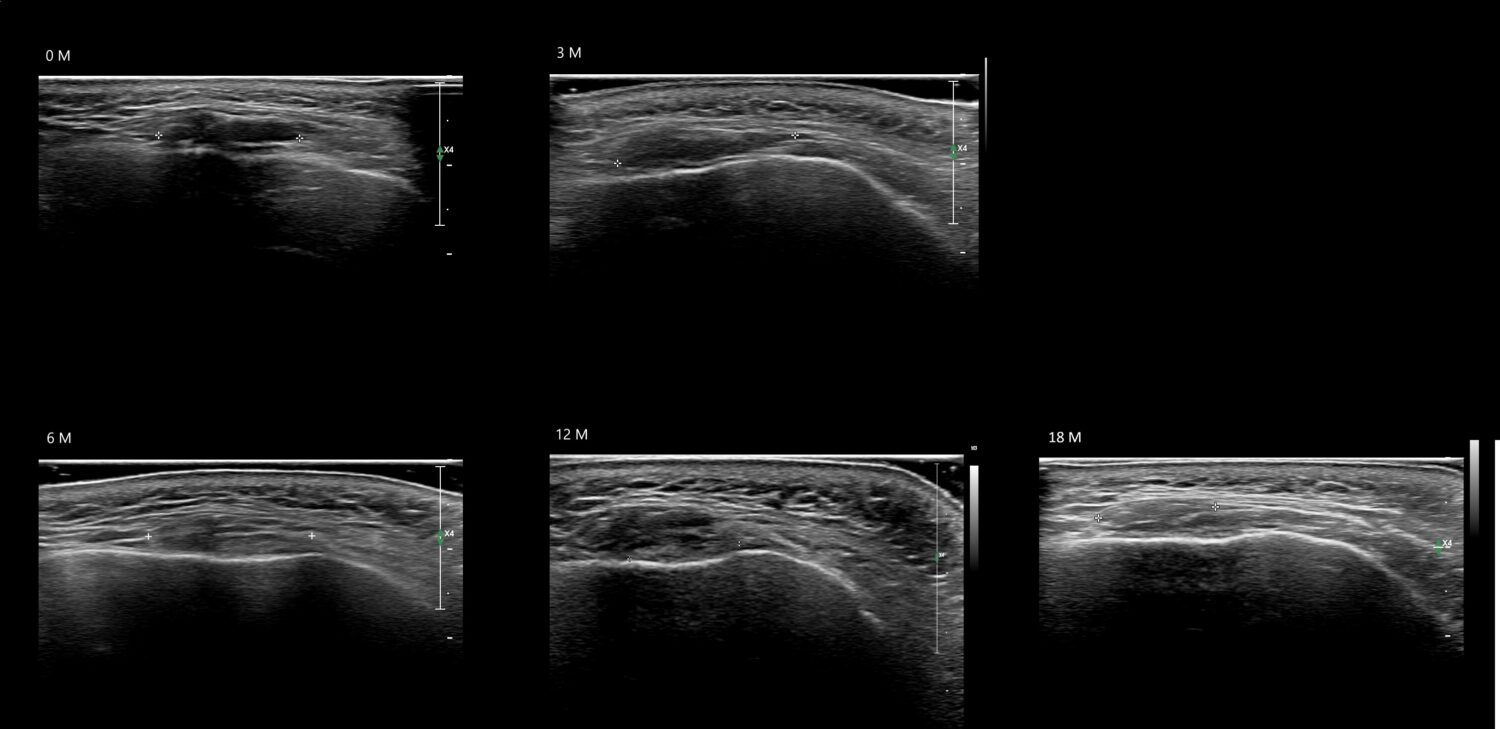

Fillers

Draw in the image on the right where the fillers are located. To check if your answer is correct, please click on the secondary image.

Fillers

Draw in the second image below where the fillers are located. To check if your answer is correct, swipe the first image to the right.